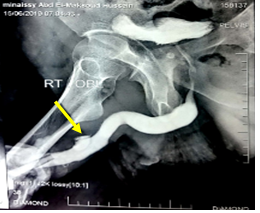

A 38 years old male patient presented to the hospital after hearing popping sound followed by asudden detumescence while having intercourse along with a profuse urethral bleeding, with no swelling or deformity of penis as shown in Figures 1&2. Local penile examination was unremarkable therefore,it was a bit misleading. Urethral catheter was inserted gently and carefully which drained clear urine andurethral injury was suspected. Patient was resuscitated and started on broad spectrum antibiotics as per the hospital`s protocol subsequently the patient had a considerableperiurethral bleeding that raised the suspicion of an additional underlying pathology; beyond the urethral injury. Ascending andmicturatingcystourethrogramin Figure 3 confirmed the presence of a tear in the tunica albuginea extending to the urethral lumen and draining the blood from the corpora cavernosa directly into the urethra, it did also show a normal filling of the anterior urethra with irregular extraurethral extravasation and finally a penile duplex ultrasound scan in Figure 4 confirmed the presence of multiple subtunical and bilateral extracorporeal small organized hematoma. Although the physical findings were not suggestive of a penile fracture, exploration was offered and advised to the patient in the view of the finding but unfortunately the patient refused to undergo exploration after settling of the urethral bleeding and he was fully and formally informed about the possibility of the associated risks mainly erectile dysfunction. The patient was self-discharged and represented 3 month later, with moderate degree of erectile dysfunction and examination revealed a 3 cm fibrotic plaque on ventral aspect of left corporeal body.

Figure 3 Showing normal filling of ant urethra with irregular extraurethral extravasation (yellow arrow).